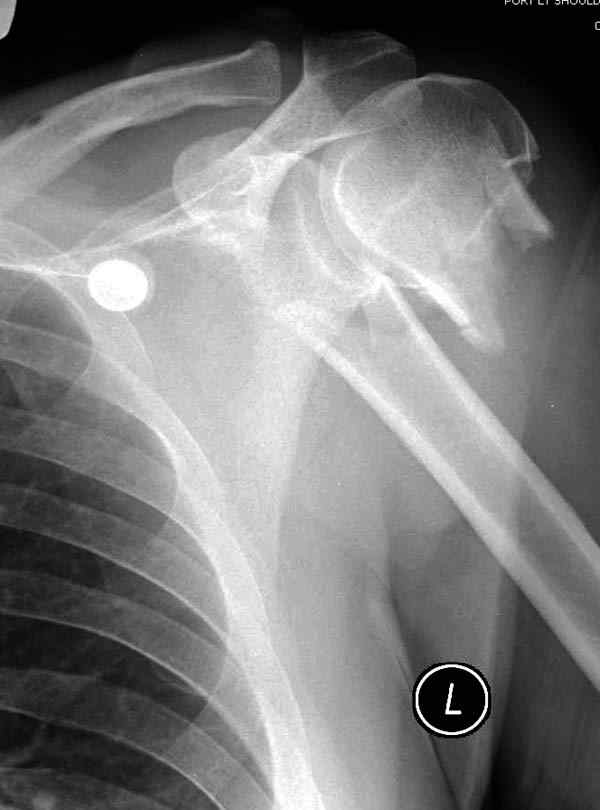

Здесь пример открытой репозиции 57 летнего с переломом плеча (1,2) смещение обнаружено на интероперационном снимке. При нормальной прямой проекция (3) угловое смещение обнаружили в аксиальной проекции (4)

После устранения смещения пластина установлена выше (5,6,7) и финальные снимки (8,9,10)